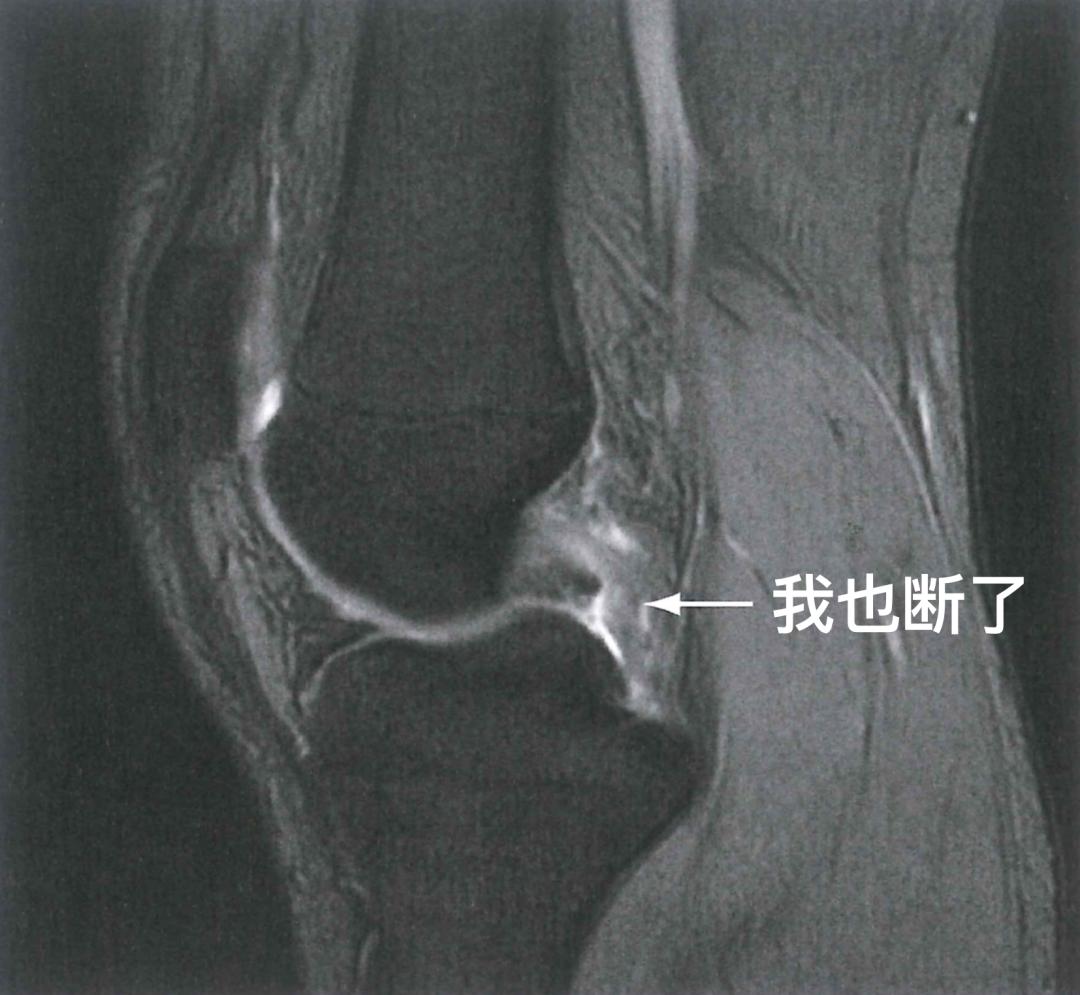

前交叉韧带能断,后交叉韧带一样也有可能被扯断。比如一不小心跌倒,膝盖没跪碎,但却有可能把后交叉韧带给跪断。骑着电瓶车在马路上摔倒,一下子膝盖敲到了地上,不少叔叔阿姨的韧带就是这样断了。类似的损伤同样可以通过膝关节MRI来诊断。这不,一做就发现,后交叉韧带真的会断!